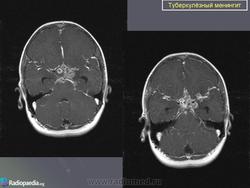

Туберкулёз ЦНС